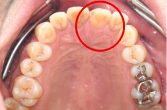

男性 Mさん 50代 (オールセラミック冠)

主訴

右上奥歯が、冷たいものにしみる。

治療内容

歯髄(神経および血管)まで到達する大きな虫歯でしたので、抜髄(歯髄を取り除く)をし、ファイバーコアをいれ、オールセラミック冠を被せました。

所感

現在、保険治療において、限定的ではありますが、大臼歯にも白い被せ物(プラスチック冠)ができるようになりました。しかし、実感としてプラスチック冠は、

- すり減りやすい。割れることがある。

- バイオフィルム(細菌およびそれから産生される副産物の塊)が付着しやすいので、歯周病および2次カリエス(被せ物と自分の歯の境目から再度虫歯になる)になるリスクが高い。

- 変色する。

という点を感じます。白い被せ物が保険の治療でできるという理由で、安易にプラスチック冠を選択し、割れたりすり減ったり、変色したらもう一度被せなおせばいいと考えるのであれば、一度立ち止まって考えてみてください。歯の量は、治療するたびに薄く少なくなり、歯根破折のリスクが高まります。もし大きな虫歯になってしまったら、最高レベルの根管治療をし、最良の被せ物であるオールセラミック冠を被せ、定期的にお口の中のクリーニングをし、同じ歯を2度と治療しないことが、歯を長持ちさせる最良の方法だと考えます。

オールセラミック冠(失活歯):¥104,500(税込)

Before

劣化したプラスチック冠

After